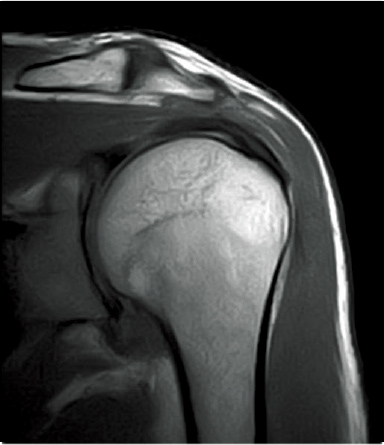

T2WI